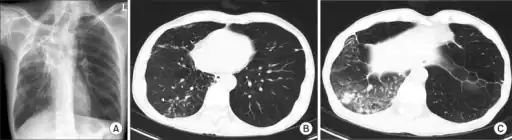

a-c)Lung disease due to Mycobacterium malmoense

- Usually infects young children with cervical lymphadenitis or adults with chronic pulmonary disease, (mostly with previously documented pneumoconiosis).